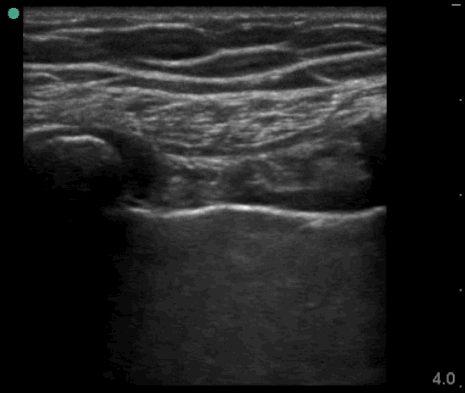

02_Lung_Ant_Left

PTX

02_Lung_Ant_Left – PTX